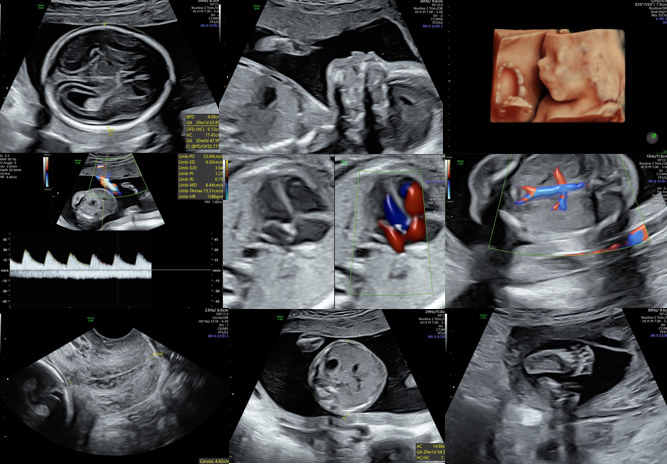

First trimester sonography has greatly improved our ability to calculate the estimated due date (EDD). However, there will be times that dating based on LMP does not match the ultrasound date. If the patient has an uncertain LMP or unreliable LMP, the earliest and most reliable sonogram should be used to establish the EDD. If the first day of her LMP is reliable, ACOG recommends redating as follows:

Second trimester: based on BPD, HC, AC and FL

First trimester ultrasound is the most accurate time frame for pregnancy dating and can increase the accuracy of the EDD even if LMP is known. If the CRL is greater than 84 mm, biometric (BPD, HC, AC, FL) parameters should be used to date the pregnancy. Mean sac diameter is not recommended for dating.